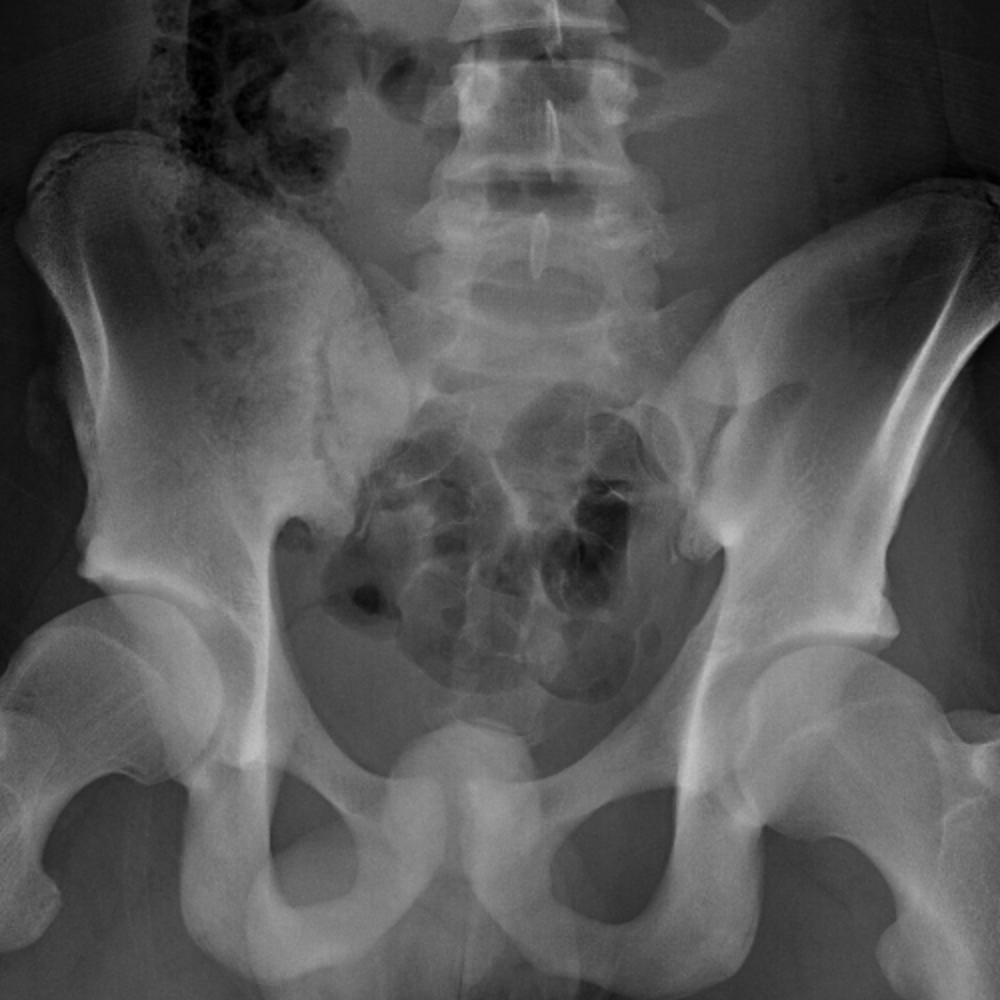

This can occur at the ligament by the application of forces external to the body (such as a fall or pull). An avulsion fracture is a fracture in which part of the bone breaks off from the rest of the bone. The asis (anterior superior ilia. An avulsion fracture occurs when a small chunk of bone attached to a tendon or ligament gets pulled away from the main part of the bone. How do i know if i have it? (obq06.38) an avulsion fracture of the anterior superior iliac spine (asis) in a adolescent athlete often occurs from forceful eccentric. Possible causes, signs and symptoms, standard treatment options and means of care and support. This can occur at the ligament by the application of forces external to the body (such as a fall or pull). Avulsion fracture of the proximal metacarpal on the palm side. Avulsion of a part of the iliac crest apophysis and the asis, downward and more outward. Anterior superior iliac spine (asis) avulsion fractures are caused by sudden pull of the sartorius muscle during forced flexion activities. Preparing for an avulsion fracture in the ankle? Most avulsion fractures heal very well without surgical intervention. Sometimes avulsion fractures can be misdiagnosed as muscle strain, so getting the correct diagnosis is important. Related online courses on physioplus. Naylor ja, goffar sl, chugg j. Keywords tensor fascia latae (tfl), anterior superior iliac spine (asis), avulsion fracture.